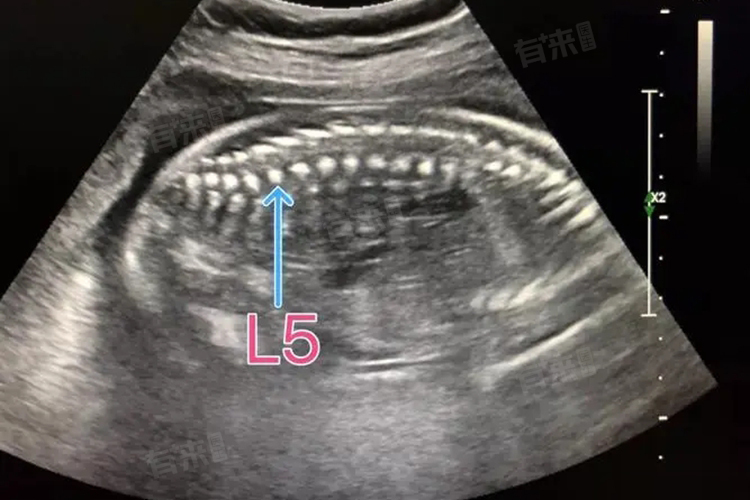

- 胎儿脊柱呈串珠状排列,此种描述意味着胎儿脊柱骨在超声图像上呈现出类似串珠的形状,彼此紧密相连,排列整齐且连续,没有缺损或断裂的情况。通常说明胎儿脊柱发育是正常的,可以排除脊柱裂、脊柱侧弯、半椎体、脊柱前突、脊柱后突等脊柱发育畸形和开放性神经管缺陷等情况。

- 胎儿的脊柱由多个椎体组成,椎体在超声图像上呈现出串珠状排列,是脊柱正常结构的一种表现。脊柱呈串珠状排列通常表示胎儿脊柱发育良好,椎体排列整齐,形态正常,没有异常弯曲或断裂。